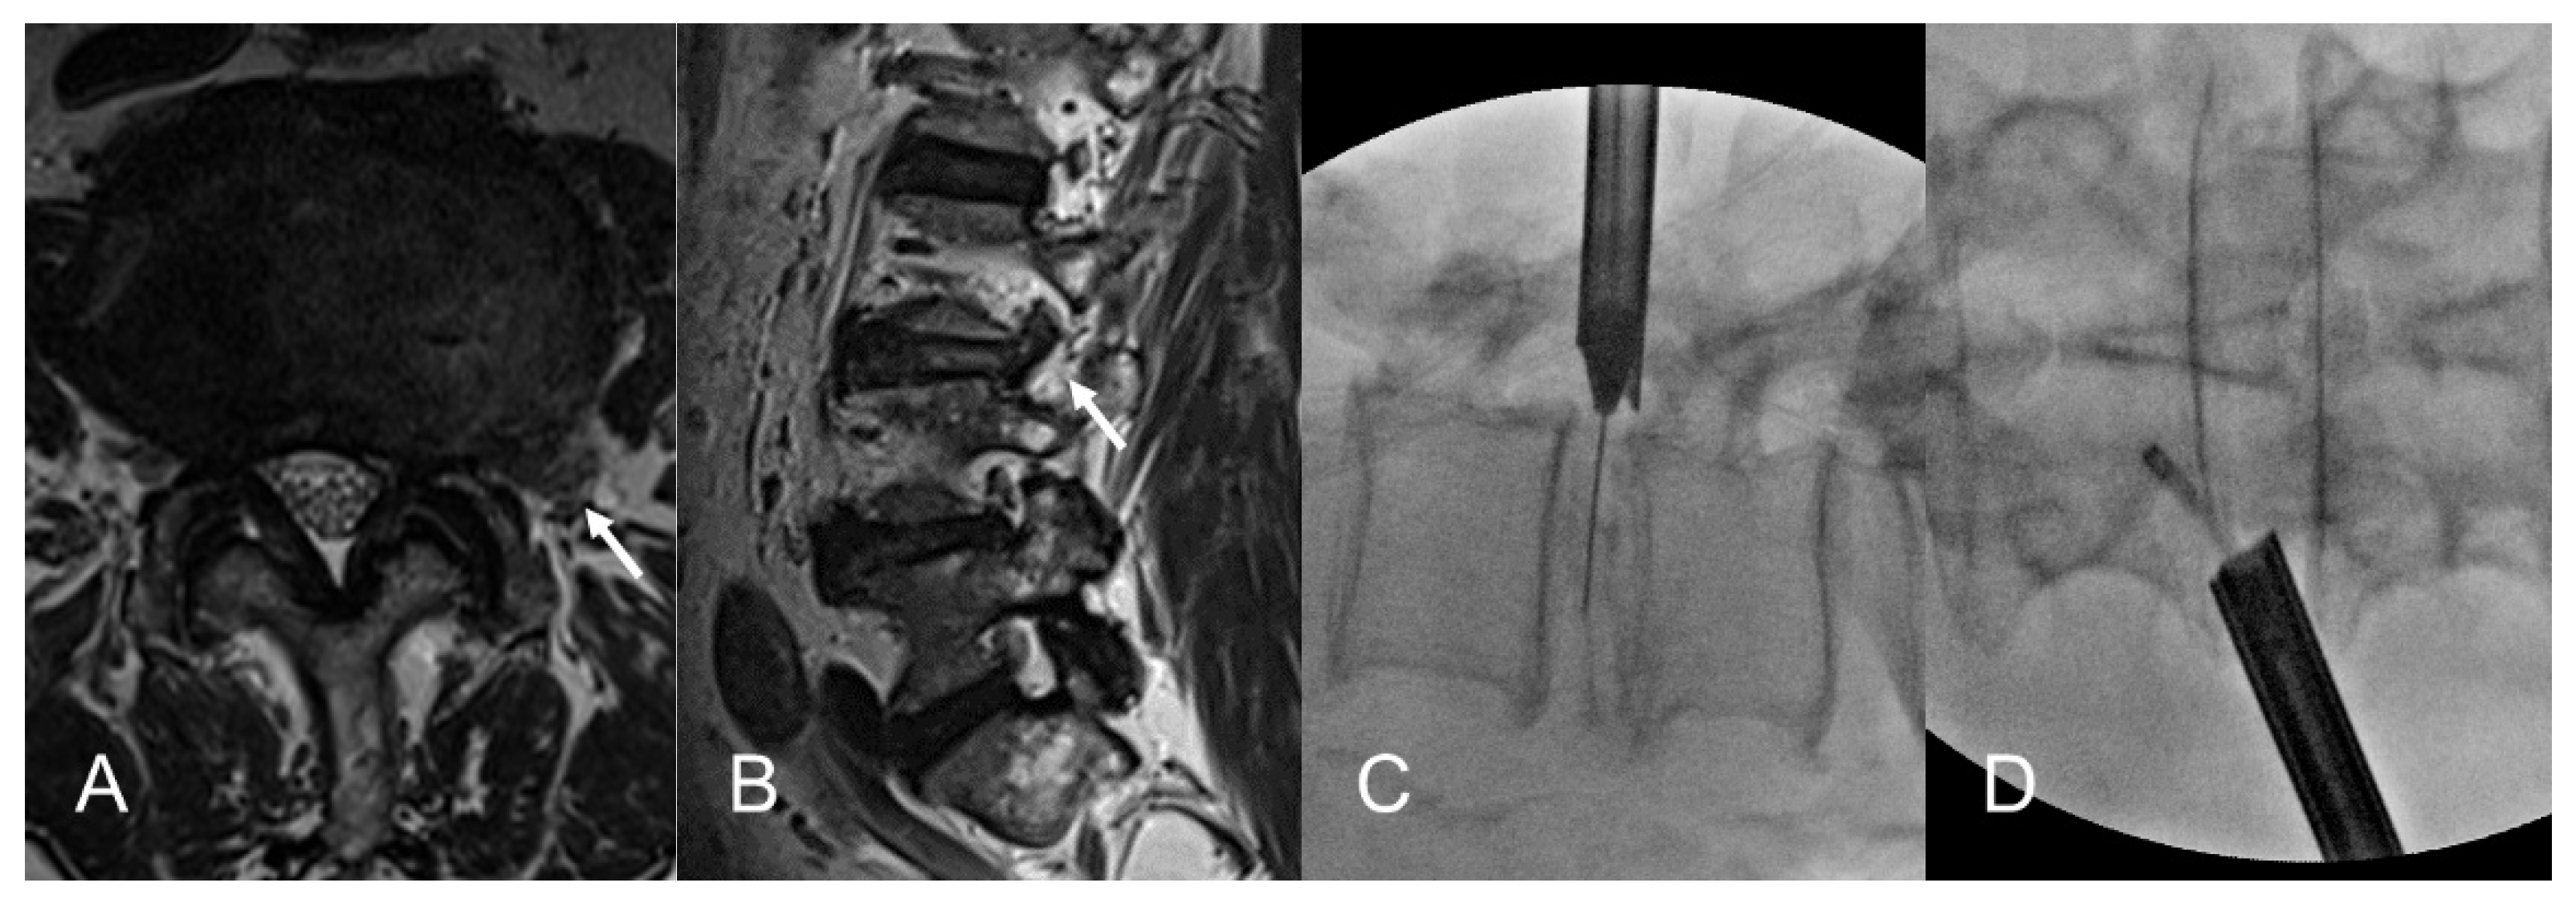

2.2.2. Transforaminal Approach under Fluoroscopic Guidance

2.2.3. Selective Discectomy under Endoscopic Visualization